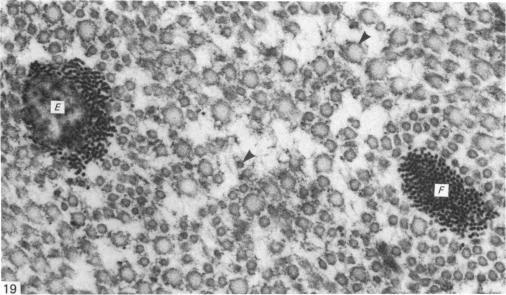

Normal human menisci obtained at autopsy (seven cases) and the injured and uninjured portions of torn menisci obtained at surgery (nine cases) were studied with the electron microscope. The surface of menisci is composed of collagen fibrils surmounted by an electron-dense surface coat. Most of the cells in menisci are chondrocytes but a few fibroblasts and cells of an intermediate form difficult to classify as either fibroblasts or chondrocytes also occur. Mast cells are found at the vascularised periphery of the meniscus. Myofibroblasts were found in the injured portions of menisci in three out of the nine cases studied. A territorial matrix containing fibrils and proteoglycan particles with associated filaments is seen around or adjacent to chondrocytes, but sometimes this matrix is sparse or absent. The interterritorial or general matrix comprises collagen fibrils of widely varying diameters (25-180 nm) set in a sparse interfibrillary matrix containing proteoglycan particles. A few mature elastic fibres and several small or immature elastic fibres and collections of electron-dense filaments are seen in the general matrix. Also seen in this region are calcified bodies and matrical lipidic debris derived by the shedding of cell processes and in situ necrosis of cells. Other features seen in the matrix of the injured portion of the meniscus include: (1) membrane-bound cystic structures; (2) parting and fraying of collagen fibrils; and (3) pools of proteoglycan particles.

对尸检获得的正常人类半月板(7例)以及手术中获得的撕裂半月板的损伤和未损伤部分(9例)进行了电子显微镜研究。半月板表面由胶原纤维组成,其上方有一层电子致密的表面涂层。半月板中的大多数细胞是软骨细胞,但也有一些成纤维细胞以及难以归类为成纤维细胞或软骨细胞的中间形态细胞。在半月板血管化的周边发现了肥大细胞。在所研究的9例中,有3例在半月板的损伤部分发现了肌成纤维细胞。在软骨细胞周围或附近可见到一个含纤维和蛋白聚糖颗粒以及相关细丝的区域基质,但有时这种基质稀疏或不存在。区域间或一般基质由直径差异很大(25 - 180纳米)的胶原纤维组成,这些纤维分布在含有蛋白聚糖颗粒的稀疏纤维间基质中。在一般基质中可见到一些成熟的弹性纤维、几条小的或不成熟的弹性纤维以及电子致密细丝的聚集物。在该区域还可见到钙化小体以及由细胞突起脱落和细胞原位坏死产生的基质脂质碎片。在半月板损伤部分的基质中还可见到其他特征:(1)膜结合的囊性结构;(2)胶原纤维的分离和磨损;(3)蛋白聚糖颗粒池。